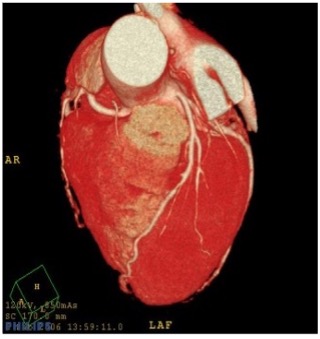

体を透過したX線を多方向から収集し、コンピューター処理によって輪切り(断層)画像を作成する装置です。脳、肺、肝臓、膵臓、血管などの臓器や、小さい病変も鮮明に描出できます。病変の正確な位置や大きさを三次元(3D)に把握することが可能で特にがんの発見、脳卒中、外傷による骨折や内臓の損傷など迅速で精密な診断が求められる場面で不可欠な検査です。

当院では2024年にキヤノン製Aquilion PrimeSPを導入しました。このCTは、Ai技術を用いた画像再構成技術AiCE を採用し、X線量を抑えつつノイズを低減し、シャープで高コントラスト・高精細なCT画像を生成することが可能です。

撮影した画像をコンピューター処理して立体的な画像として表示できます。